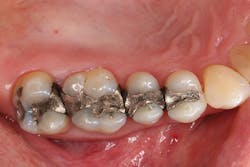

Figure 1: A 51-year-old male patient presented with multiple failing side-by-side amalgam restorations in Nos. 2 through 5 that exhibited marginal leakage, requiring replacement.